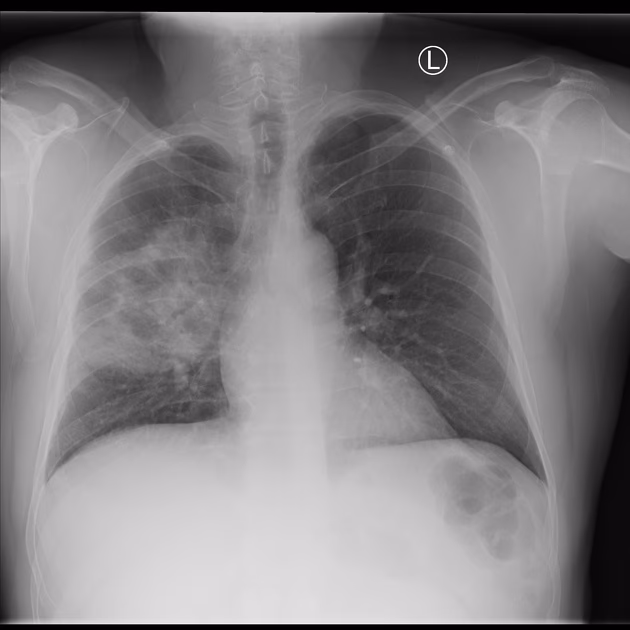

Et røntgenbillede af brystkassen er den vigtigste test til at bekræfte diagnosen. Ved lobær lungebetændelse vil røntgenbilledet typisk vise en tydeligt afgrænset, hvid skygge (konsolidering) i en hel lungelap. I nogle tilfælde kan en CT-scanning være nødvendig for at få et mere detaljeret billede af lungerne, især hvis der er mistanke om komplikationer.